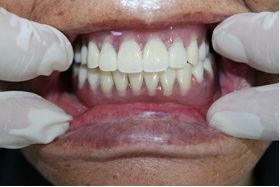

病例展示:全口種植桿卡修復(fù)(種植活動(dòng)聯(lián)合修復(fù)/半固定種植牙技術(shù))

病歷一:

患者,女性,73歲。

主訴:多牙體缺失,余留牙體松動(dòng)不適,進(jìn)食效率低下(困難),要求治療。

治療方案:完善相關(guān)化驗(yàn)檢查,松動(dòng)牙拔除,并行全口種植桿卡修復(fù)治療。

術(shù)前片/術(shù)后片

選復(fù)合基臺(tái)(上頜)/選復(fù)合基臺(tái)(下)

桿卡試戴(上頜)/桿卡試戴(下頜)

咬合確定 /治療結(jié)束